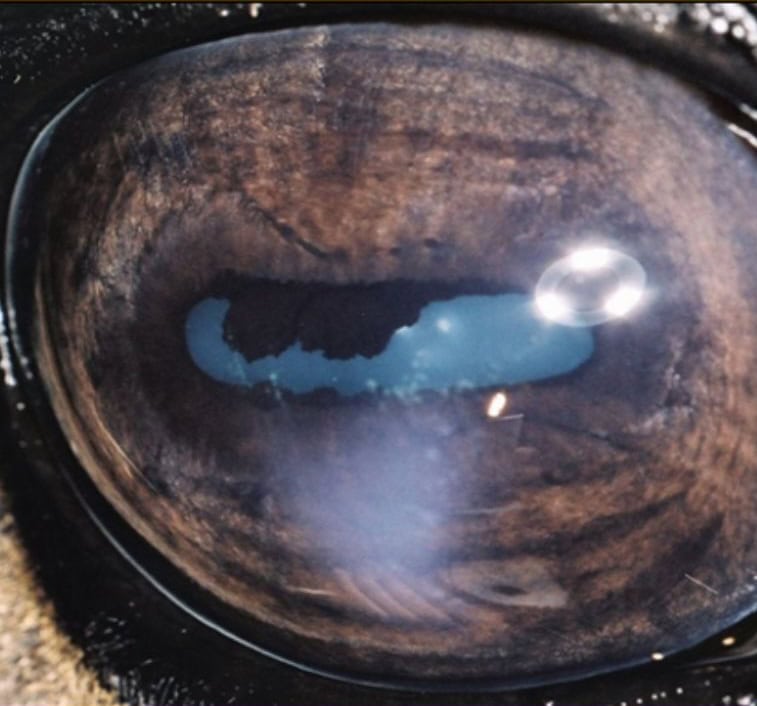

Clinical Approach to Uveitis with Caryn E. Plummer, DVM, DACVO

Confidently identify, differentiate, and manage uveitis in horses – from acute flare-ups to complex recurrent cases – while minimising vision loss and safeguarding long-term comfort.